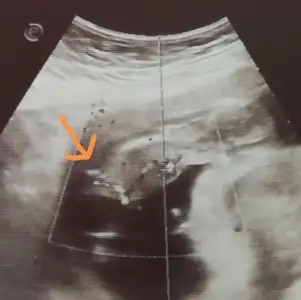

Ben ilk hamileliğimde 2 doz oldum bunda da bi doz yapalım dedi ebe, ben yine yaptıracağımArkadaşlar biraz araştırdım tetanoz aşısı hakkında ama olumsuz bi şey görmedim yine de olumsuz birşey duyarsanız bilgilemdirirseniz sevinirim